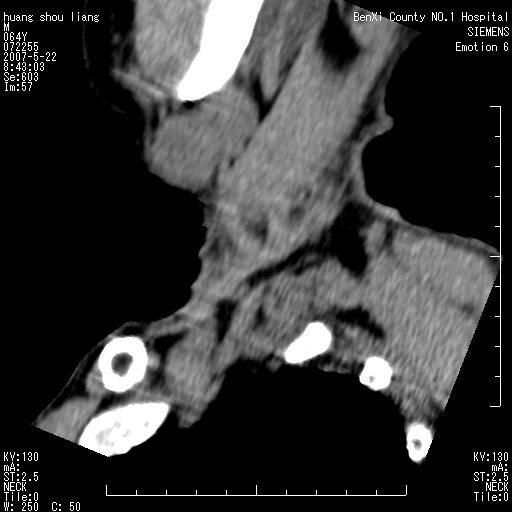

标题: CT8337:颈部包块8年,颈部CT和VRT,请讨论。

男性,64岁。颈部包块8年。最近增大。

对不起大家,可能是片子发太多有点乱,正常腮腺在下颌角的外侧,颌下腺在下颌体的中部内侧,本例在下颌角内侧偏下,和腺体一点关系都没有,从vrt和mpr上可以很明显看出来,再者肿块是好多粘连在一块的,大家在仔细看看,左侧可能也是吧,我还是考虑为肿大的淋巴结融合在一块,但性质??????

多考虑颌下腺混合瘤恶变,建议进一步检查,另外楼主重建图像很漂亮。

大家好,病理结果出来了,如大家所说,颌下腺混合瘤。

画个图共同讨论一下解剖关系。